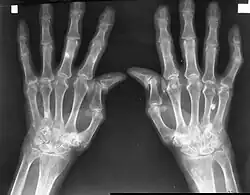

![]() Dłonie pacjentów ze zmianami w przebiegu RZS |

RZS jest układową chorobą tkanki łącznej, która charakteryzuje się nieswoistym, symetrycznym zapaleniem stawów (dotyczącym głównie małych i średnich stawów), zmianami pozastawowymi i powikłaniami układowymi. Przebiega z okresami remisji i zaostrzeń. Prowadzi do destrukcji stawów, ich zniekształcenia, przykurczów i upośledzenia funkcji, a ostatecznie bywa najczęstszą przyczyną niepełnosprawności, postępującego inwalidztwa i przedwczesnej śmierci.

W przebiegu RZS stwierdza się najczęściej symetryczne zapalenie stawów rąk:

- śródręczno-paliczkowych

- międzypaliczkowych bliższych

Występuje ból i obrzęk zajętych stawów z ograniczeniem ich ruchomości. Charakterystycznym objawem jest sztywność poranna stawów, ustępująca stopniowo podczas ruchu. Jest to silny ból stawów oraz ich sztywność i obrzęk, które uniemożliwiają wykonywanie nawet najprostszych czynności, takich jak mycie, ubieranie czy swobodne poruszanie się. Symptom ten powoduje uczucie silnej bolesności przy próbie ściśnięcia dłoni i ograniczenie możliwości ruchu. Długość trwania sztywności zależy od nasilenia procesu zapalnego[9] - może trwać od kilku minut do kilkunastu godzin. Wcześnie dochodzi do zaników mięśni międzykostnych, glistowatych i mięśni kłębu kciuka. Maleje siła mięśni, siła i pewność chwytu dłoni. Często występuje zajęcie ścięgien i pochewek ścięgnistych. Uszkodzenie stawu i aparatu więzadłowego powoduje charakterystyczne odgięcie łokciowe (ulnaryzację) palców ręki, podwichnięcie dłoniowe paliczków dalszych, zmiany typu łabędziej szyjki i palca butonierkowego; może dojść do przeprostów. Powikłaniem może być również powstanie torbieli Bakera.

Ważnym objawem reumatoidalnego zapalenia stawów są guzki reumatoidalne, czyli twarde, niebolesne zgrubienia, występujące najczęściej w tkance podskórnej, które mogą też pojawić się w narządach wewnętrznych, jak płuca, serce czy nerki. Charakterystyczne dla RZS w zaawansowanych stadiach rozwoju są dystrofie mięśniowe. Dochodzi wtedy także do deformacji stawów międzypaliczkowych, wysięków w stawach łokciowych, uszkodzenia stawów biodrowych, rdzenia kręgowego i korzeni nerwowych. Skóra w miejscach dotkniętych zmianami chorobowymi jest chłodna, wilgotna i ścieńczała.